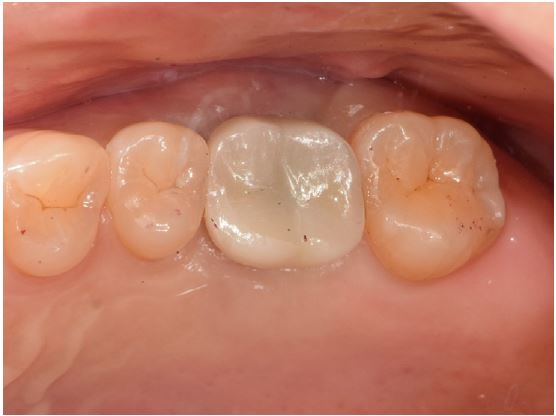

At the next visit, the cast post was tried in (Fig. 5B), and the internal and marginal fits were checked clinically and radiologically (Fig. 6). The cast post was passively fit into the fixture, and the margin was set with an equigingival finish line. The upper prosthesis was made of a monolithic zirconia using the computer-aided design/computer-aided manufacturing (CAD-CAM) technique. The master cast was scanned with a model scanner (T500; Medit, Seoul, Korea), and the monolithic restorations were designed digitally, with narrow occlusal table width and minimal cusp inclination to minimize the offset load.

The zirconia prosthesis was tried in, and oral evaluation and adjustment were performed sequentially. Occlusion adjustment was performed according to the general concept of implant-supported prostheses. The occlusion was meticulously evaluated on a continuous basis to avoid the non-axial force vector that could lead to implant failure. At centric occlusion, the degree of the implant occlusal force was similar to that of the adjacent natural teeth.

After adjustment, the inner side of the fixture was rinsed with chlorohexidine and normal saline and dried using absorbent paper points (ProTaper Gold Absorbent Point; Dentsply Sirona). The cast post was bonded to the fixture with a resin-based cement (PANAVIA™ F 2.0; Kuraray Noritake Dental, Tokyo, Japan). Cement was applied to the post, and the post was seated in the post space with finger pressure. Excess cement was removed, and periapical radiographs were taken to check whether the cement had remained or not. The zirconia prosthesis was cemented with a resin-modified glass ionomer cement (FujiCEM® 2; GC Corporation, Tokyo, Japan) (Fig. 7).